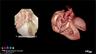

This CME teaching activity provides detailed information on the evaluation of the normal fetal heart both from an anatomic and functional approach. In keeping with progress in this field, detailed information on the use of three-dimensional ultrasound in fetal echocardiography and cardiac imaging in the early gestation is presented. The course also provides a comprehensive evaluation of various cardiac malformations, involving abnormalities of the cardiac chambers and the outflow tracts.

Congenital heart disease is the most common congenital malformation with a significant impact on neonatal morbidity and mortality. Prenatal diagnosis and management of congenital heart disease is a collaborative effort between maternal–fetal medicine specialists and pediatric cardiologists. The renowned course faculty represents the specialties, and all are actively involved in caring for pregnancies complicated with fetal cardiac abnormalities.